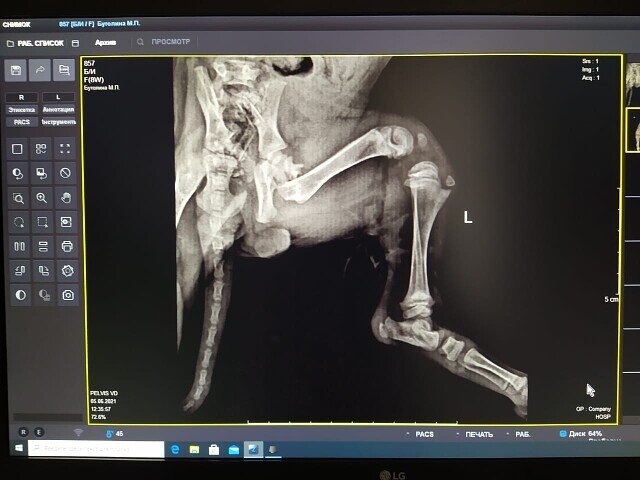

Очередную нашу печаль-беду нашла в Лиманских степях Маша Корчагина. Маша увидела коробку с глазами и не смогла проехать мимо. Щенок сидел в коробочке и уже даже не плакал. Девушка вытащила малышку из коробки и обнаружила кровоподтеки и опухоль в паху. Поставила крошку на землю и увидела, что та не может ходить. Задняя лапа болталась на коже, как будто тряпочка.

-2

Маша приняла решение не оставлять там щенка. Страшная мошка не давала ни одного шанса на выживание. Добавить сюда лис и волков, и понятно, до утра крошка не дожила бы при любом раскладе. Посадила в машину и позвонила мне. Я даже для порядка не сопротивлялась. Ясно же, что стало очередным нашим приобретением. К сожалению, крошку успела сильно искусать мошка и клещи. На рентгене она в буквальном смысле теряла сознание.

-3

Но сложный перелом не давал даже пары дней на восстановление сил. Андрей Степанович - один из лучших хирургов нашего города решил рискнуть и прооперировать щенка сразу же. Больше недели кроха была между небом и землей, и только на днях стало ясно, мы победили.

Вот так вот. Человек предполагает, а Бог располагает...  И рентгенолог, и Андрей Степанович сказали, что щенка однозначно ударили ногой в пах, причем с большой силой. Ее увечье - дело рук недочеловека. За что? За то, что подбежала просить помощи? За щенячью доверчивость? Эх вы, сами не живете и другим не даете.